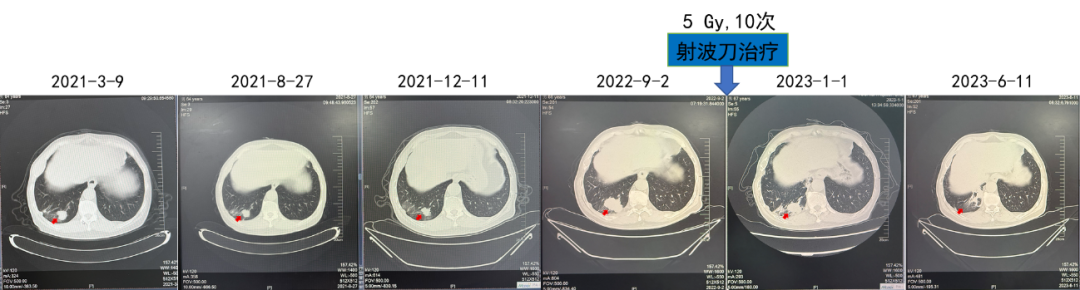

疗效:肺部病灶疾病稳定(4年)。对侧肾上腺病灶部分缓解(4年)。

(射波刀治疗)